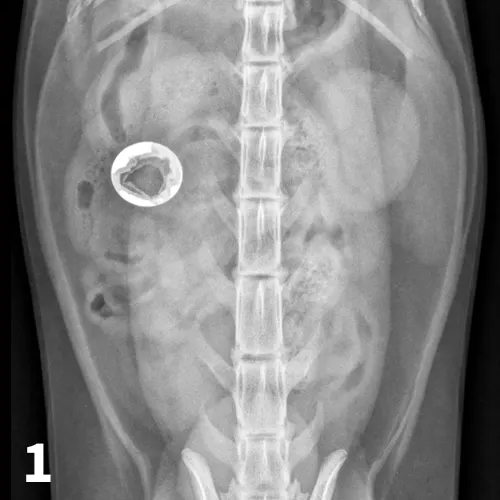

A ventrodorsal abdominal radiograph showing a round metallic object in the small intestine.

FIGURE 1

VD abdominal radiograph of a 1-year-old cat with a 2-day history of vomiting and a nonobstructing metallic foreign body. A coin with a radiolucent center caused by erosion is present within the small intestinal loops in the right midabdomen. No dilated loops of small intestine are seen to indicate mechanical obstruction.